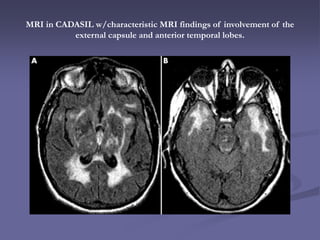

MRI in CADASIL w/characteristic MRI findings of involvement of the

external capsule and anterior temporal lobes.

MRI

 Most specific finding to

differentiate CADASIL

from ischemic

leukoaraiosis

 T2 hyperintenisties in

anterior temporal pole